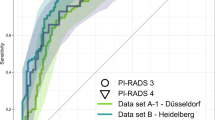

The PROSTATEx and PI-CAI challenges aim to evaluate the performance of AI models for csPCa detection and classification. Launched in 2014, the PROSTATEx challenge has been the only public benchmark for this task to-date. More than 1,765 entries have been submitted during the challenge, with the maximum value of the area under the curve at receiver operating characteristic analysis currently at 0.95. Meanwhile, in the PI-CAI challenge provides the largest training (n ≈ 9,000; of which 1,500 cases will be made public), validation (n ≈ 100), and testing (n ≈ 1,000) datasets to-date, with a study design and reference standard established in conjunction with multi-disciplinary radiology, urology and AI experts in the domain. PI-CAI also includes an international reader study with 63 radiologists (42 centers, 18 countries; 1–23 years of experience reading prostate MRI, median 9 years) till-date, to assess the clinical viability of stand-alone AI relative to radiologists.